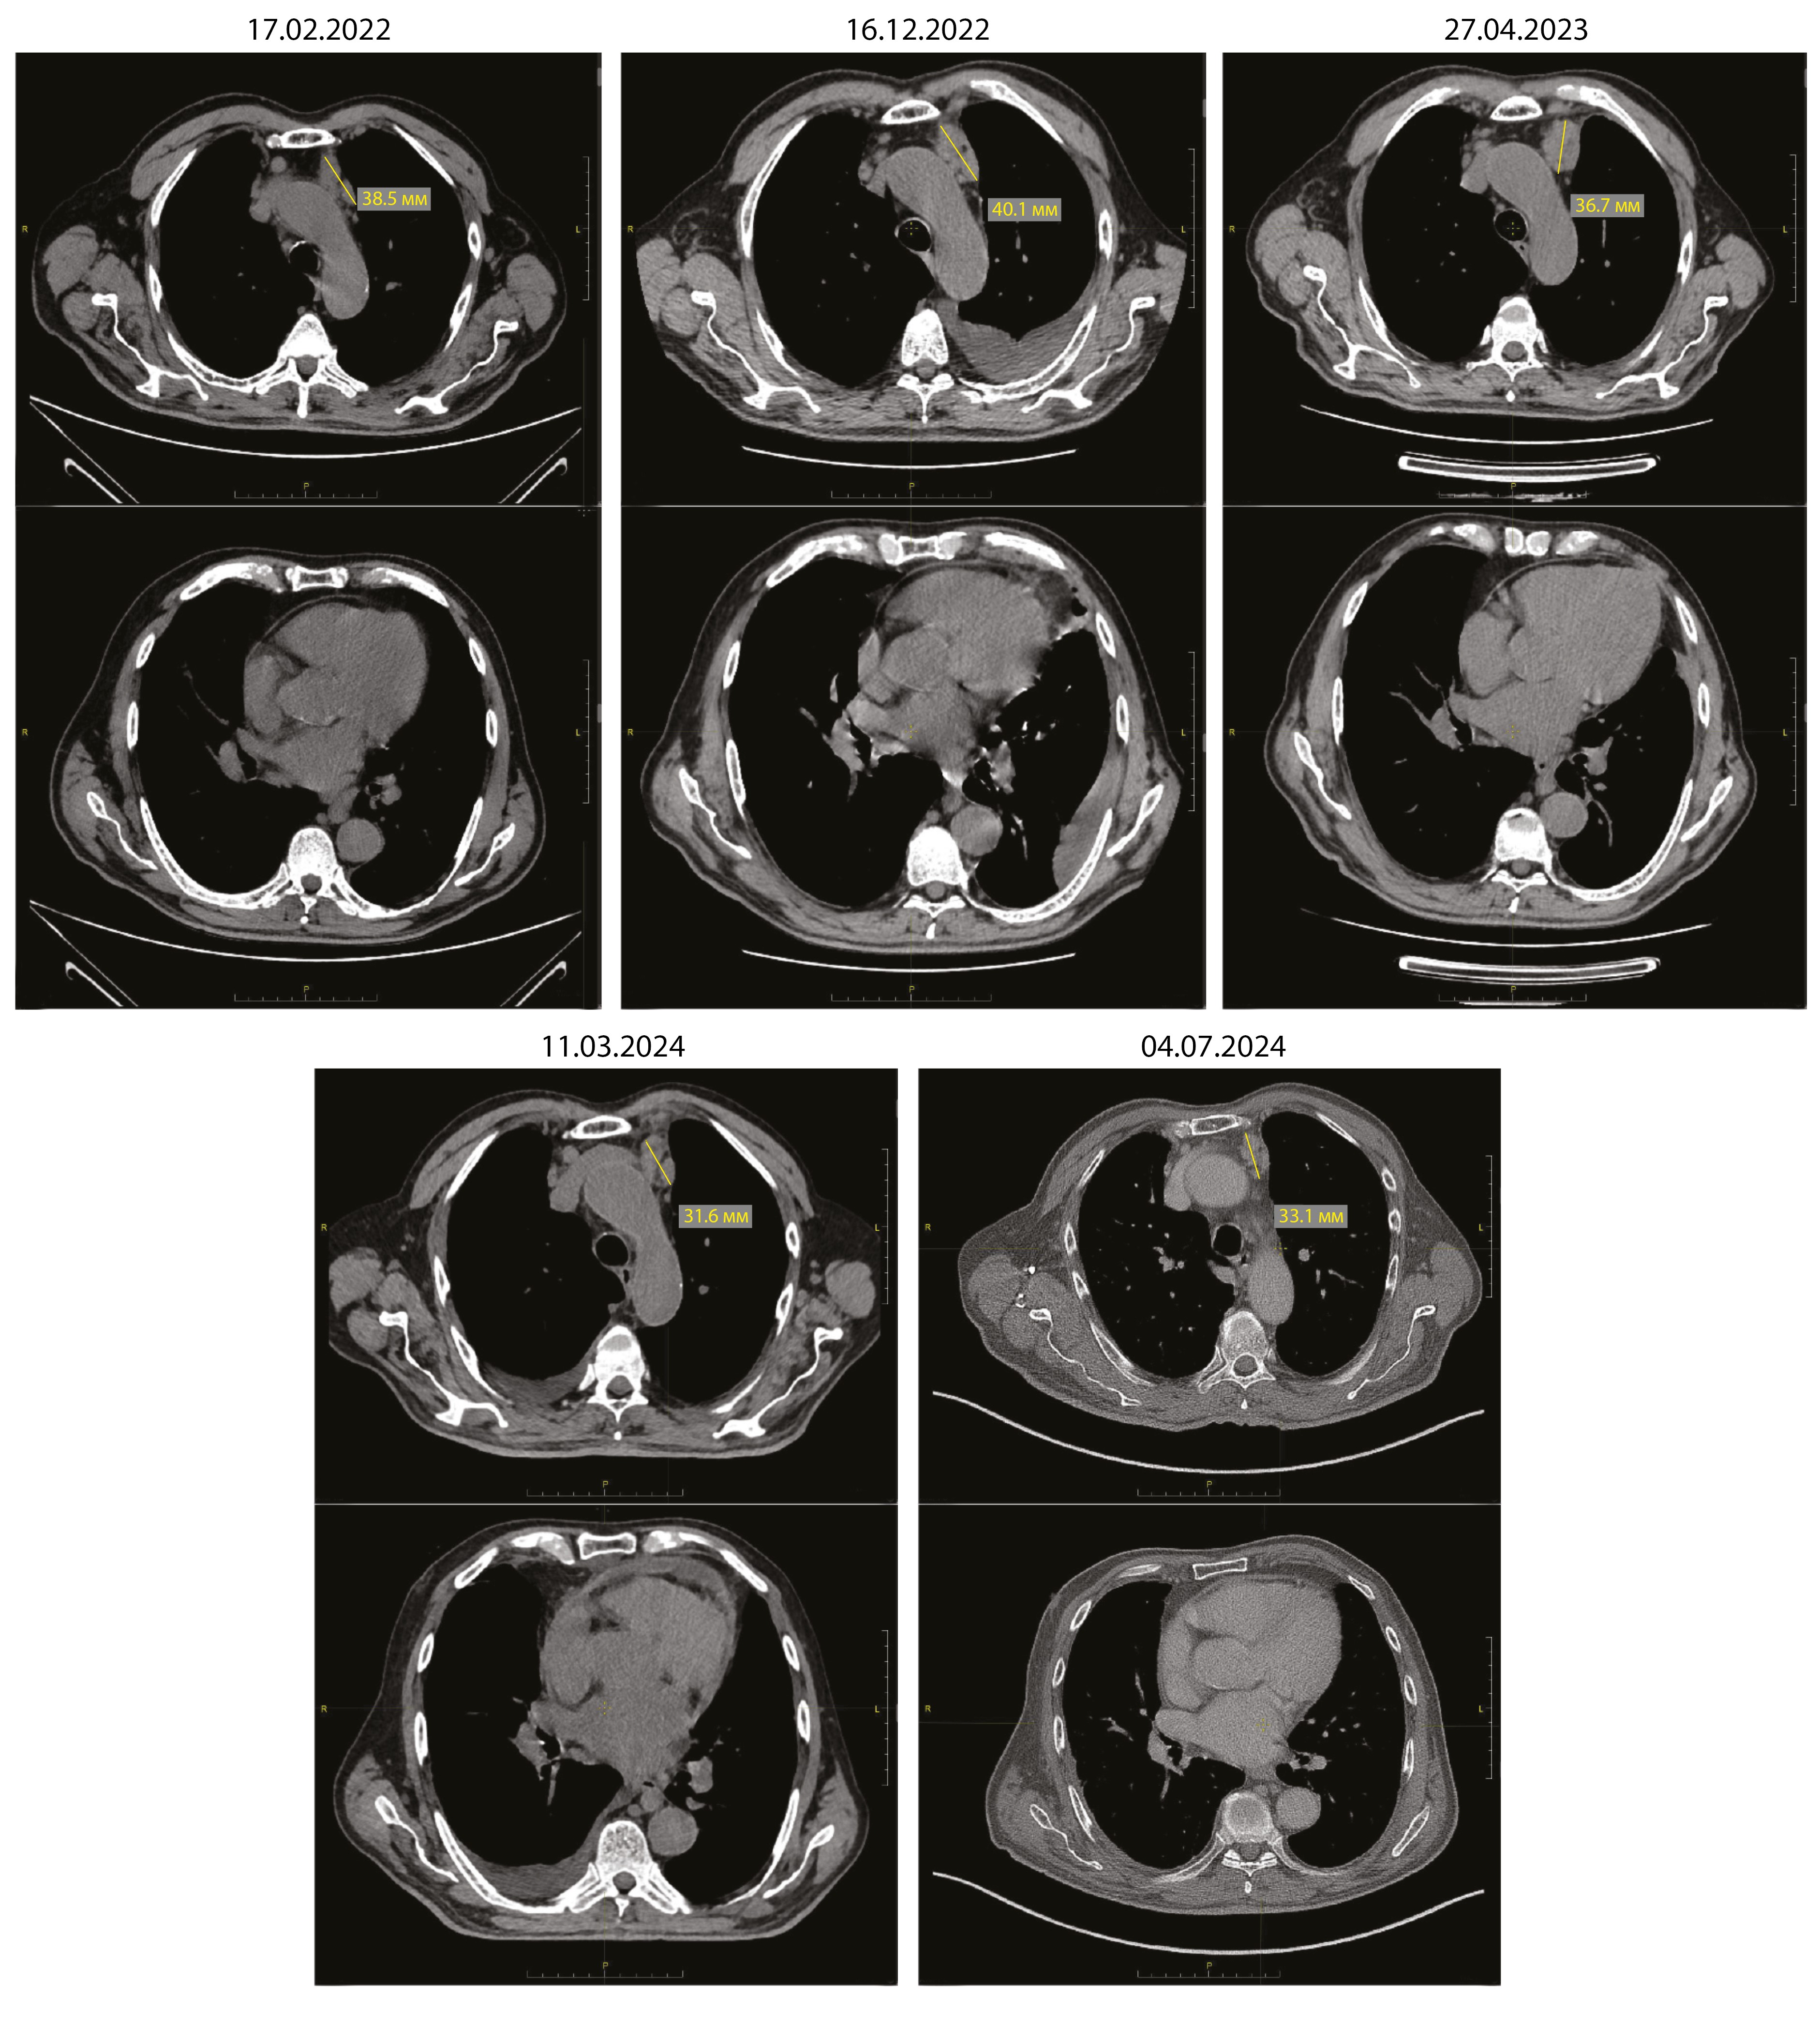

За 2 года существования лимфаденопатии средостения (КТ ОГК за это время выполнена 7 раз, рис. 4) и неспецифических изменений в периферической крови диагноз установлен не был, несмотря на обращение к онкологу.

Рис. 4. Серия КТ-изображений, отражающая длительность существования внутригрудной лимфаденопатии. В верхних рядах изображений – аксиальные срезы на уровне пакета лимфатических узлов в верхнем средостении (размер обозначен желтым маркером), в нижних – срезы, отражающие состояние перикарда. Белой стрелкой отмечена жидкость в правой плевральной полости, белым треугольником – накопление жидкости в полости перикарда в марте 2024 г.